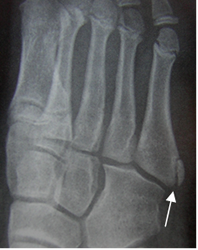

Fig 51. Núcleo de crecimiento.

Rx Oblicua. Núcleo de crecimiento en la base del 5º metatarsiano, de bordes escleróticos

y definidos, que no debe confundirse con fractura.